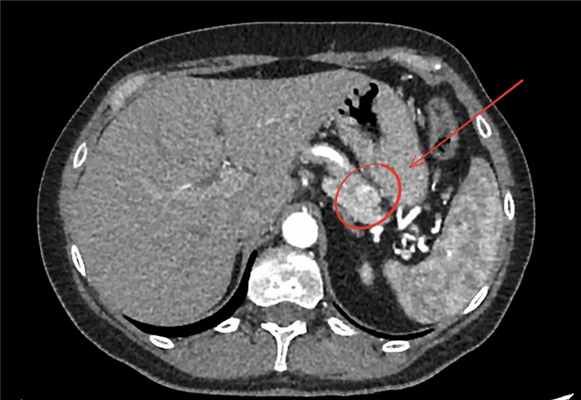

Рис.1 Инсулинома на компьютерной томографии

Выполнение КТ или МРТ с контрастированием помогает выявить инсулиному в поджелудочной железе и точно определить ее местоположение. Однако, в некоторых случаях обнаружение инсулиномы на КТ или МРТ может быть затруднительным. Тогда используется эндоультрасонография или эндоскопическое УЗИ.